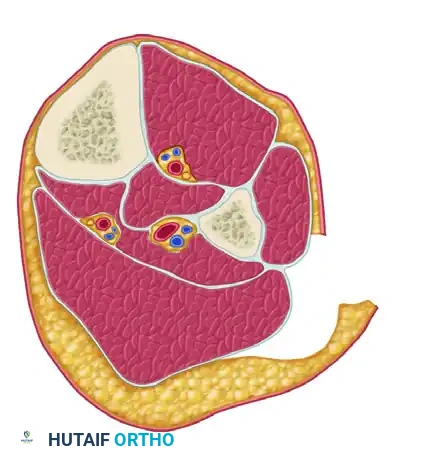

FASCIOTOMY FOR ACUTE COMPARTMENT SYNDROME OF THE THIGH

The thigh is anatomically divided into three distinct compartments: anterior, posterior, and medial. Because the thigh compartments possess a larger volume and greater compliance than those of the leg, thigh compartment syndrome is relatively rare. However, when it occurs, it is typically the result of massive blunt trauma, femur fractures, or prolonged compression.

The standard approach for thigh decompression utilizes a single extensive lateral incision to access both the anterior and posterior compartments, with a secondary medial incision reserved for specific medial compartment involvement.

Step 2: Releasing the Anterior Compartment

Deepen the dissection through the subcutaneous tissues to expose the glistening white fibers of the iliotibial band. Make a straight, longitudinal incision directly in line with the skin incision through the iliotibial band and the underlying fascia lata. This maneuver effectively decompresses the anterior compartment.

Step 3: Accessing the Posterior Compartment

Carefully reflect the vastus lateralis muscle off the lateral intermuscular septum. Retract the muscle belly medially and anteriorly.💡 CLINICAL PEARL: During the reflection of the vastus lateralis, you will encounter multiple perforating branches from the profunda femoris artery. It is critical to meticulously identify, clamp, and coagulate or ligate all perforating vessels to prevent massive postoperative hemorrhage, which could paradoxically recreate a hematoma-driven compartment syndrome.

Step 4: Releasing the Posterior Compartment

Once the lateral intermuscular septum is clearly visualized, make a 1.5-cm initiating incision through the septum. Using heavy Metzenbaum scissors, extend this fascial release proximally and distally for the entire length of the surgical incision to fully decompress the posterior compartment.

Step 5: Evaluating the Medial Compartment

After the anterior and posterior compartments have been thoroughly released, it is imperative to measure the intracompartmental pressure of the medial (adductor) compartment using a handheld manometer or arterial line setup. If the pressure remains elevated (Delta P < 30 mm Hg), a separate longitudinal medial incision must be made to release the adductor fascial envelope.